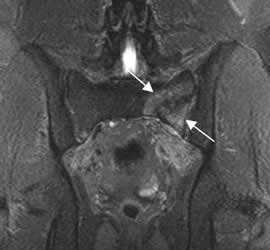

Fig 53. Avulsión.

A: RM coronal en T1 y B: RM coronal en STIR. Cambios inflamatorios sobre la tuberosidad isquiática izquierda por avulsión. Hay retracción en el origen de los isquiotibiales.